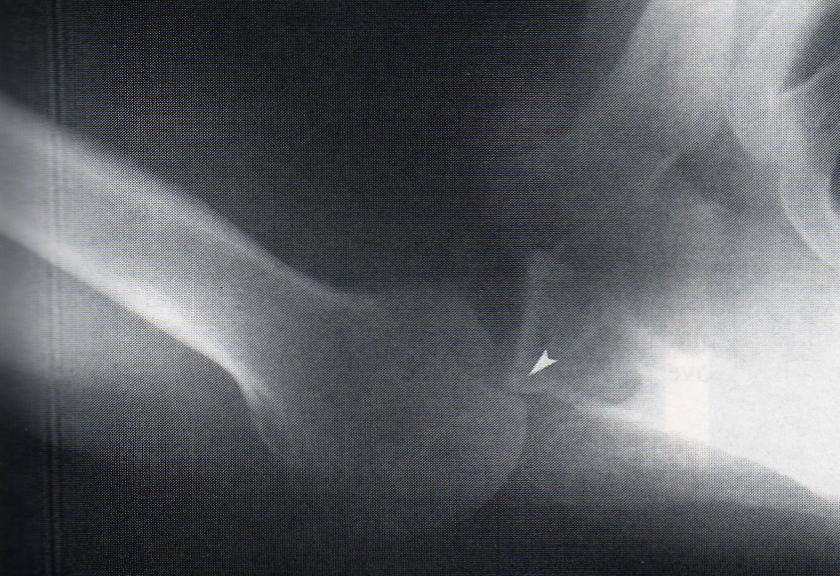

this deformity is due to repeated anterior dislocations (and on every baord exam ever per Lauri)

● Hill-Sachs Fx/Deformity

Hill-Sachs Fx/Deformity